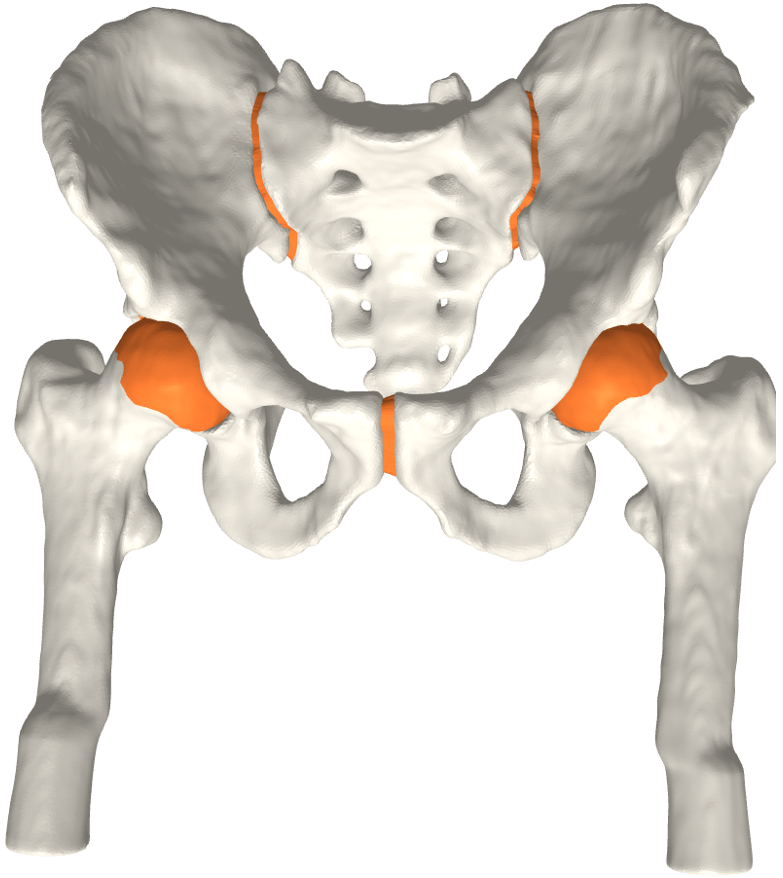

Figure 3: The final cartilage generated by our method for a femur (a), (b) and a pelvis (c). Notice how the cartilage aligns with the anatomical lines.

The FE analysis results show that the generated models produce smooth stress patterns in a pseudo stance without any geometry-related convergence issues. As mentioned in section 4, these results only serve as a verification test of simulation properties. We need a more advanced simulation setting to model a real stance position. We leave this for future work. Moreover, we believe that minor modifications will estimate the shoulder joint cartilage since it has a similar ball-in-socket structure. Fig. 5 shows early evidence of generalization. In contrast, other joints, such as the knee joint, are challenging. We leave other joint types for future work.

Refer to caption

(a)

(b)

(c)

Figure 5: a) All generated cartilages. Zoom boxes highlight the pubic and sacroiliac joint cartilages. b) Shoulder joint cartilage c) Femoral and tibial cartilage in the knee joint. Bone models are acquired from available datasets [3, 5, 4].